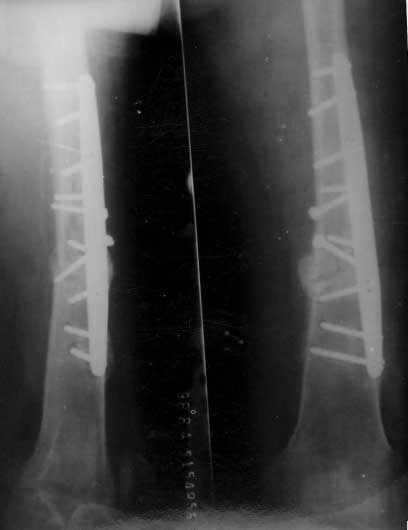

股骨骨折术后2年,骨不连形成

BMP复合骨髓注射2次,骨折愈合